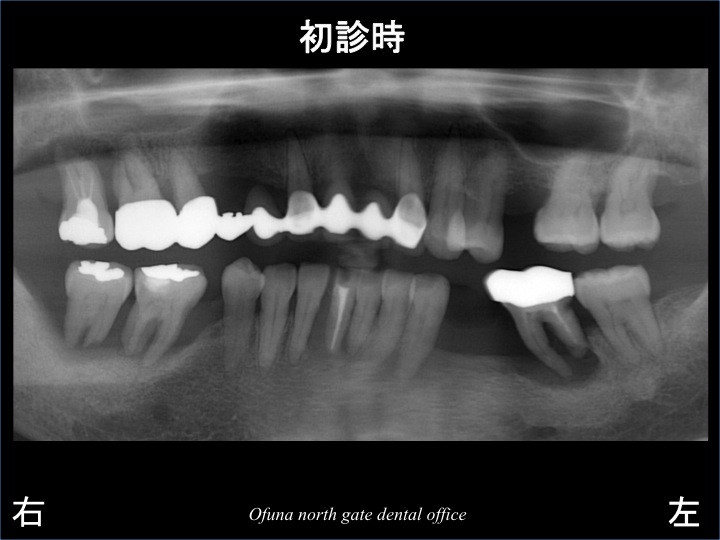

以下は、初診時のレントゲン写真です。

レントゲン等の 検査の結果、骨の吸収がかなり起こっていました。